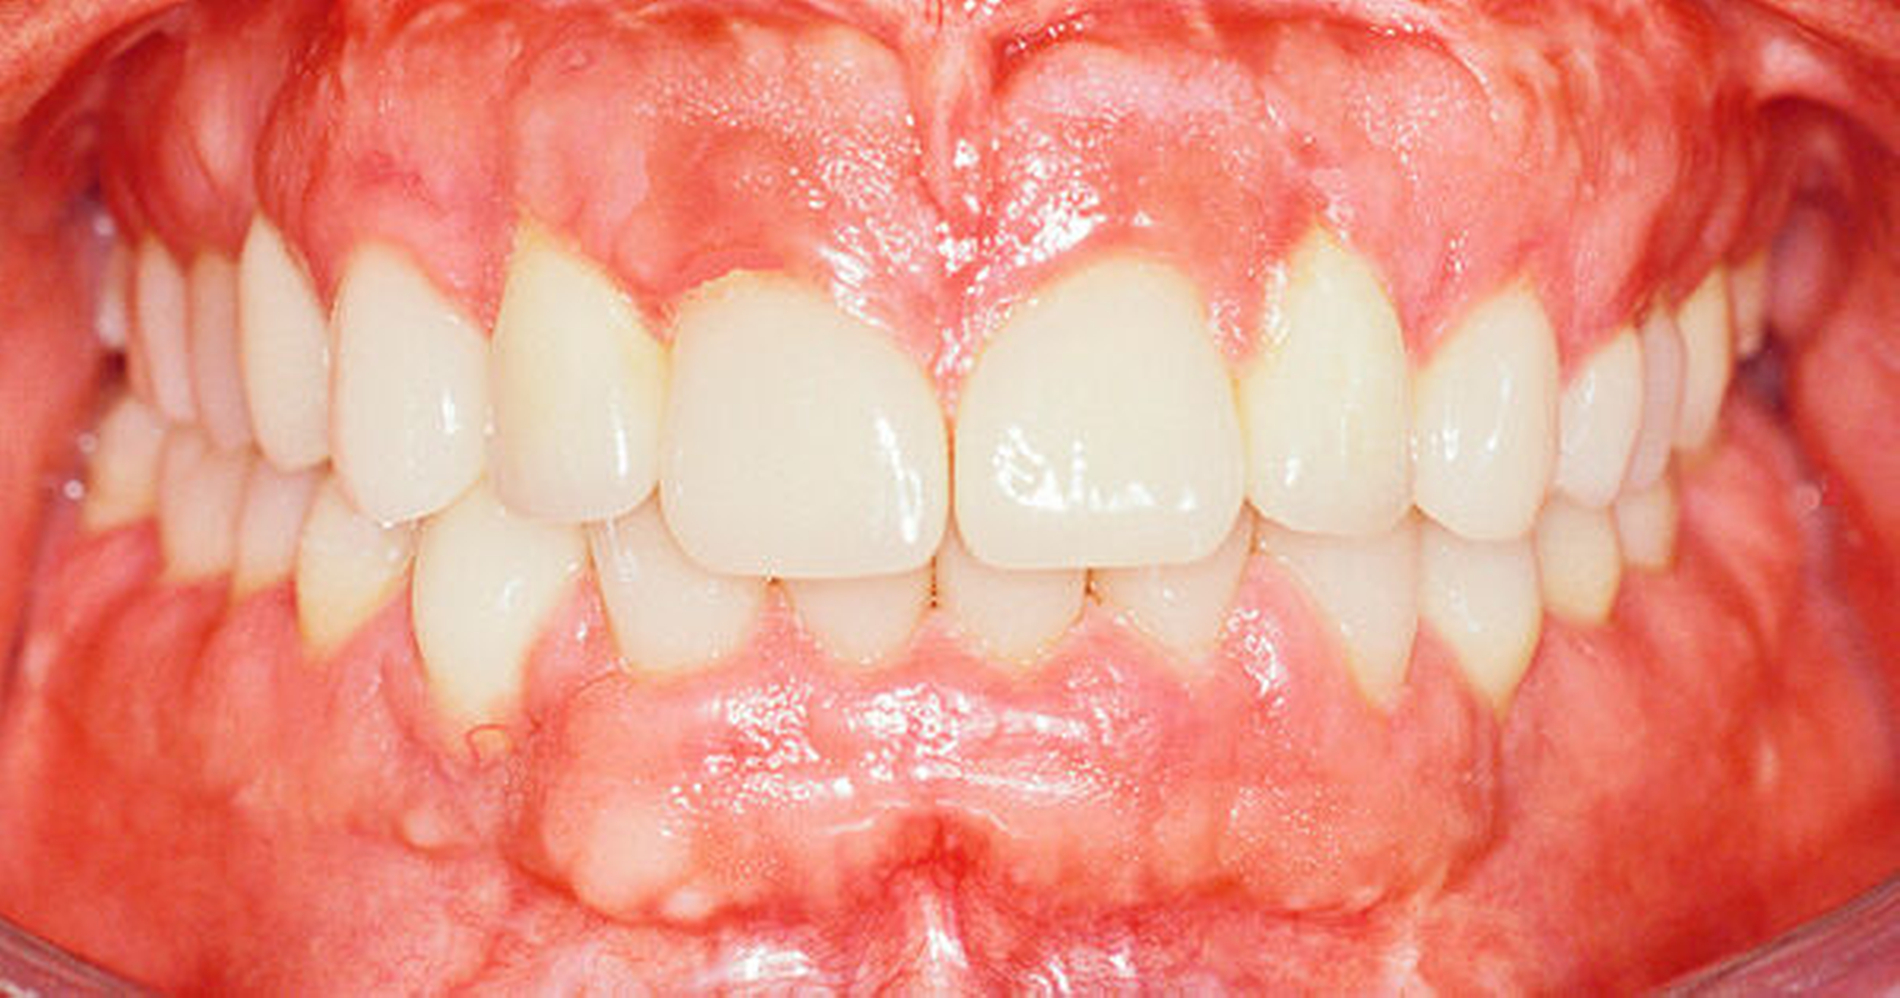

Die Abbildungen 11a und 11b, 12a und 12b sowie 13 dokumentieren das Ergebnis. Die Patientin trägt nachts Retainer im Ober- und im Unterkiefer. Sie ist sehr zufrieden mit dem natürlichen Aspekt ihrer neuen Zähne, den verbesserten Gesichtsproportionen sowie der stabilen Okklusion und kommt dreimonatlich zum Recall mit Kontrolle und Mundhygiene.